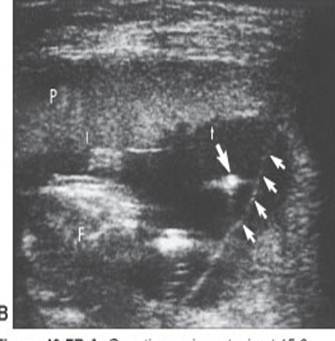

Measurement of incompetent cervix